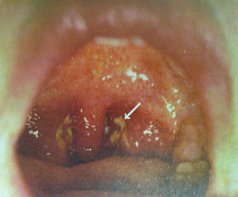

Die Symptome von Streptokokkenangina (bakterielle Infektion)

und Mononukleose (Virusinfektion) sind ähnlich mit Halsweh,

Übelkeit, Fieber, Schüttelfrost, Kopfweh, geschwollene

Lymphknoten und geschwollene Mandeln. Die genaue Bestimmung,

welche Krankheit es ist, ist nur mit Bluttest und mit einem

Abstrich der Rachenschleimhaut möglich (4 Strategien, S.309).

Steptokokkenangina

Angina

ist je nach Blutgruppe verschieden heilbar, weil die

Immunsysteme verschieden stark sind [8] |

Die Streptokokkenangina hat weitere Symptome, u.a.

Hautausschlag. Die "Schulmedizin" behandelt mit Antibiotika

und Aspirin. Dabei wiederholt sich die Infektion oft, und die

"Schulmedizin" weiss keine Lösung des Problems (4 Strategien,

S.309).

Die Blutgruppen 0 und B erholen sich schneller [wegen des

aktiveren Immunsystems] (4 Strategien, S.309). Bei den

Blutgruppen A und AB sind die Erreger nur schwer zu

vertreiben. Massnahmen sind:

-- Blutgruppendiät

-- Mundspülung von Salbei und Gelbwurztee (Berberitze, mit

Berberin), desinfiziert Hals und Mandeln, kann Wiederholungen

verhindern, schmeckt bitter, aber wirkt, der Rachenraum kann

eventuell auch mit einem Halsspray eingesprayt werden

-- abwehrsteigernde Ergänzungsstoffe: Beta-Karotine, Vitamin

C, Zink, Sonnenhut (4 Strategien, S.310).